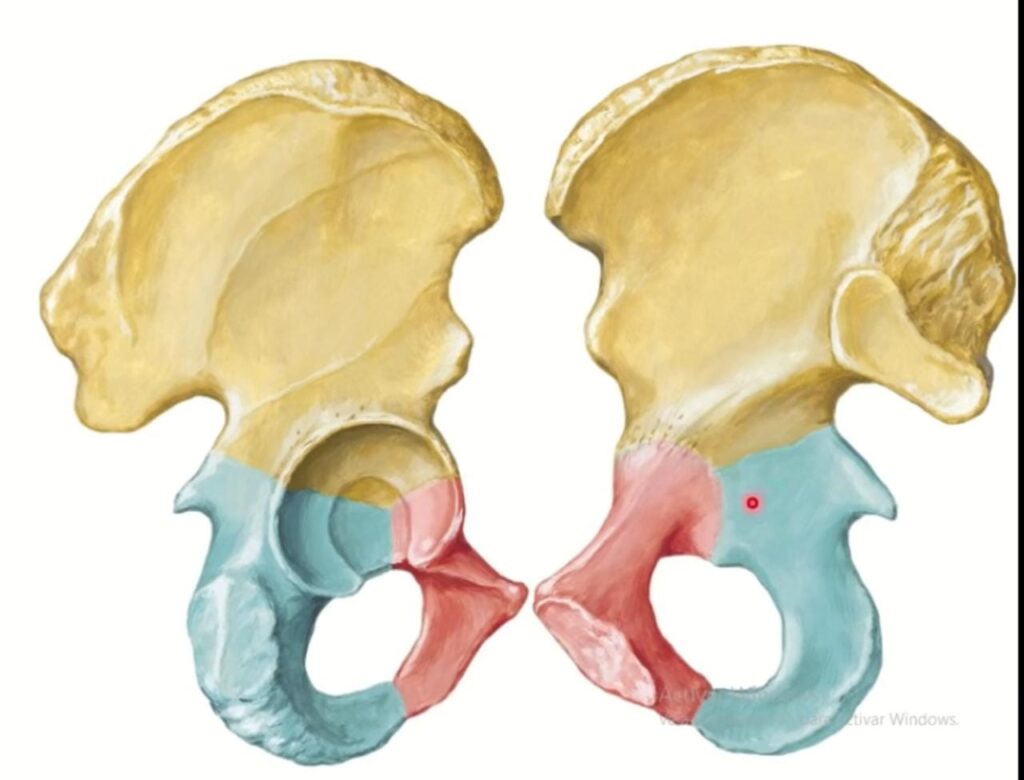

¿Qué huesos delimitan la cavidad pélvica?

Los huesos coxales, el sacro y el cóccix desempeñan un papel fundamental en la formación y delimitación de la cavidad pélvica, una estructura en forma de embudo ubicada en la…